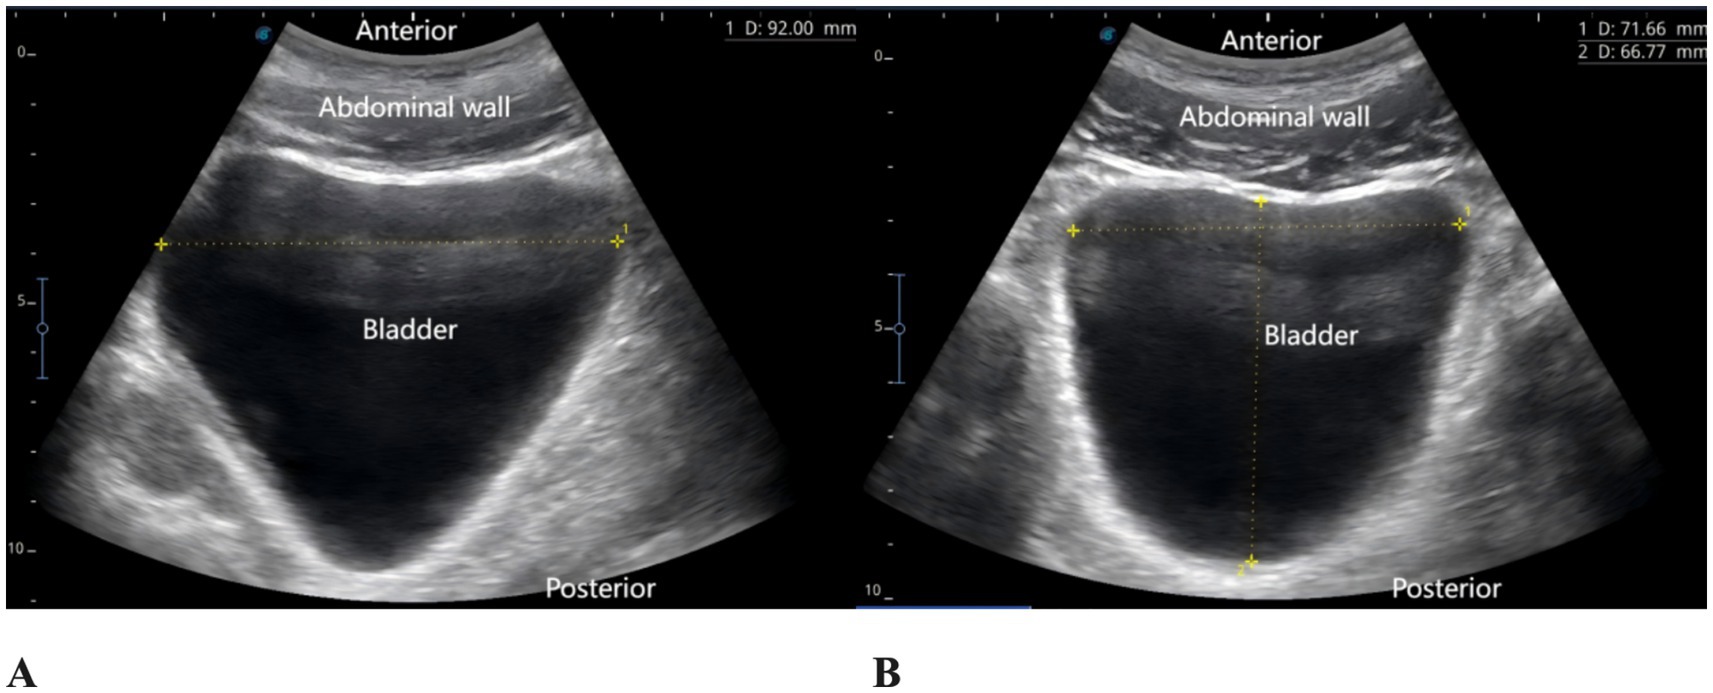

Figure 3

Bladder ultrasound images. (A) Sagittal view. (B) Transverse view.

The patient reported severe pain in the right hip (VAS score of 9) upon arrival at the emergency department of the hospital (15:00 on May 27, 2025). Physical examination revealed external rotation deformity of the right lower limb, positive tenderness at the midpoint of the inguinal ligament and the greater trochanter, and restricted flexion and extension of the hip joint. Movement of the toes remained intact, and distal perfusion and sensory function of the foot were normal. Urgent laboratory tests—including complete blood count, coagulation profile, and electrocardiogram—showed no significant abnormalities. Subsequently, an ultrasound-guided pericapsular nerve group (PENG) block was administered by the anesthesiologist using 20 mL of 0.2% ropivacaine for right hip analgesia (8). Ten minutes after the block, the patient reported that his hip pain had decreased to a VAS score of 1. At that time, his urinary function was normal, with no signs of urinary retention. He was then transferred to the orthopedic ward for further management. At 18:00 that evening, the patient reported significant relief of right hip pain but complained of severe pain localized to the L5 region, with a VAS score of 9, rendering him unable to lie in the supine position. The anesthesiologist instructed the patient to assume the prone position, and bedside ultrasound scanning of the lumbosacral region was performed. The ultrasound image revealed the presence of spinal fusion hardware from L4 to S1, appearing as a hyperechoic linear structure. A 12 cm longitudinal surgical scar was noted along the midline of the lumbosacral region. The location of the L5 transverse process was identified and marked based on preoperative CT imaging in conjunction with real-time ultrasound guidance. After disinfection of the puncture site, a high-frequency linear transducer (6–13 MHz, SonoSite, USA, Model, S-series) covered with a sterile adhesive drape was placed vertically in the sagittal position on the marked L5 transverse process. 2 mL of 2% lidocaine was used for local anesthesia at the skin puncture site. An 18G × 100 mm needle (Contiplex type D, Braun Melsungen, Germany) was inserted using an in-plane, cranial-to-caudal approach, with the tip advanced into the fascial plane between the erector spinae muscle and the L5 transverse process. After the needle tip contacted the L5 transverse process, 3 mL of normal saline was injected to confirm correct placement. Following negative aspiration for blood or air, 20 mL of 0.2% ropivacaine was injected into the fascial plane between the erector spinae muscle and the transverse process. Ultrasound demonstrated a hypoechoic, elongated spread of the local anesthetic between the deep surface of the erector spinae muscle and the transverse process (Figure 2). The same procedure was performed on the contralateral side. Since this was a routine ultrasound-guided fascial plane block, no injection pressure monitoring device was used. However, during the procedure, the anesthesia assistant observed unusually high resistance to injection. Twenty minutes after the bilateral ESPB, the patient experienced significant alleviation of lumbosacral pain (VAS score of 2), with intact sensory and motor function in both lower limbs. One hour later (at 19:00), the patient complained of a strong urge to void and suprapubic fullness but was unable to urinate. Neurological examination revealed no sensory or motor deficits in either lower limb. A bedside ultrasound by a urologist confirmed significant bladder distension (Figure 3). Urinary catheterization was performed, yielding 700 mL of urine within 5 min, followed by immediate relief of bladder discomfort. At 5:00 the following morning, the patient reported gradual return of sensation in the lumbosacral region and described bladder stimulation caused by the indwelling urinary catheter. After an additional hour of close observation, during which urine output remained normal, the catheter was removed. Spontaneous voiding function was subsequently restored. After the analgesic effects of the PENG and ESPB subsided, the patient continued to receive multimodal analgesia. His baseline regimen included oral tramadol hydrochloride and transdermal fentanyl patches, with additional oral celecoxib administered as required. On hospital day 3, the patient underwent closed reduction and internal fixation for the right femoral neck basal fracture under general anesthesia using a laryngeal mask airway. The patient received our institution’s standard multimodal analgesia regimen for hip surgery, which included oral celecoxib (200 mg once daily) and a patient-controlled intravenous analgesia (PCIA) pump containing oxycodone (100 mg diluted in 0.9% saline to a final concentration of 1 mg/mL, no continuous background infusion, bolus dose 0.03 mg/kg, lockout interval 5 min). No additional regional block was performed, and urinary retention did not recur. Postoperative X-rays on postoperative day 1 and day 5 confirmed satisfactory fracture reduction, and no further episodes of acute urinary retention occurred during this period. The patient was discharged on postoperative day 6. He reported that the regional blocks provided substantial pain relief, allowing him to tolerate positioning and daily care before surgery. Although he experienced some discomfort due to urinary retention, he expressed overall satisfaction with pain management and the recovery process, considering it acceptable compared with the severe pain he had before the blocks. A detailed timeline of the patient’s hospitalization, interventions, and clinical course is summarized in Table 1.